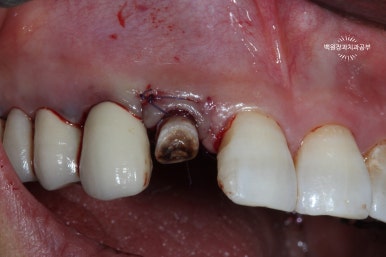

오른쪽 위 가쪽 앞니 (측절치)가 뿌리만 남아있는 것을 보실 수 있을겁니다. (잔존 치근)

왼쪽: periotome을 사용하여 발치 시행, 오른쪽: 치아를 완전히 뽑지 않고 위치를 수정.

외과적 정출술의 핵심은

남은 치아 뿌리(잔존치근)가 부러지지 않고 온전히 탈구가 되어 나와주어야 한다는 것입니다.

이를 위해 제가 있었던 치주과에서는 페리오톰(periotome)이라는 아~주 얇은 기구를 사용하여 치아를 주변 치조골에서 분리해내어 조심스럽게 약간 빼어내곤 했습니다.